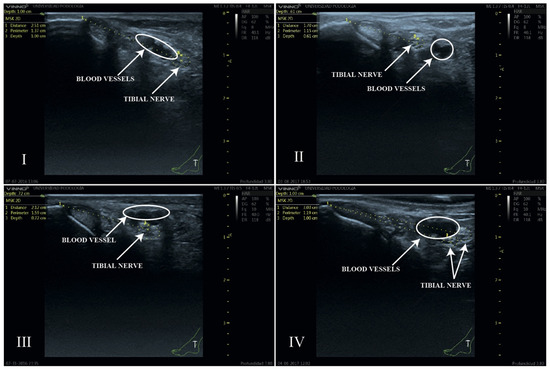

Background: Clinical procedures involving the tibial nerve (TN) are complex procedures due to its deep anatomical position and the variability of its course in the retromalleolar region. Few studies have described the ultrasound characteristics of the TN in vivo. This study aims to describe the ultrasound position of the TN and its relationship with the posterior tibial artery (PTA) at the retromalleolar level, evaluating the influence of sex, weight, height, and body mass index (BMI). Methods: A cross-sectional ultrasound study was performed on 100 volunteers. Anthropometric variables were recorded. Ultrasound measurements included the TN perimeter, distance from the medial malleolus to the TN center, depth, and spatial relationship with the PTA. Statistical analyses included Student’s t-test, ANOVA, Chi-square test, and Pearson’s correlation coefficient, with a significance level of p < 0.05. Results: The mean distance from the TN to the medial malleolus was 2.17 cm, and its mean depth was 0.91 cm. The most common anatomical pattern was Type I (TN posterior to the PTA) (60%). Sex influenced TN position, with men showing greater distances from the medial malleolus to the TN center (2.42 vs. 1.99 cm) and women showing greater depth from the skin surface to the upper edge of the tibial nerve perimeter (0.94 vs. 0.86 cm). Weight (p = 0.004), height (p < 0.001), and ankle circumference (p = 0.006) correlated significantly with TN location, whereas BMI did not (p = 0.253). Conclusion: These findings provide clinically relevant reference data that may improve the precision and safety of different tibial nerve procedures. Full article